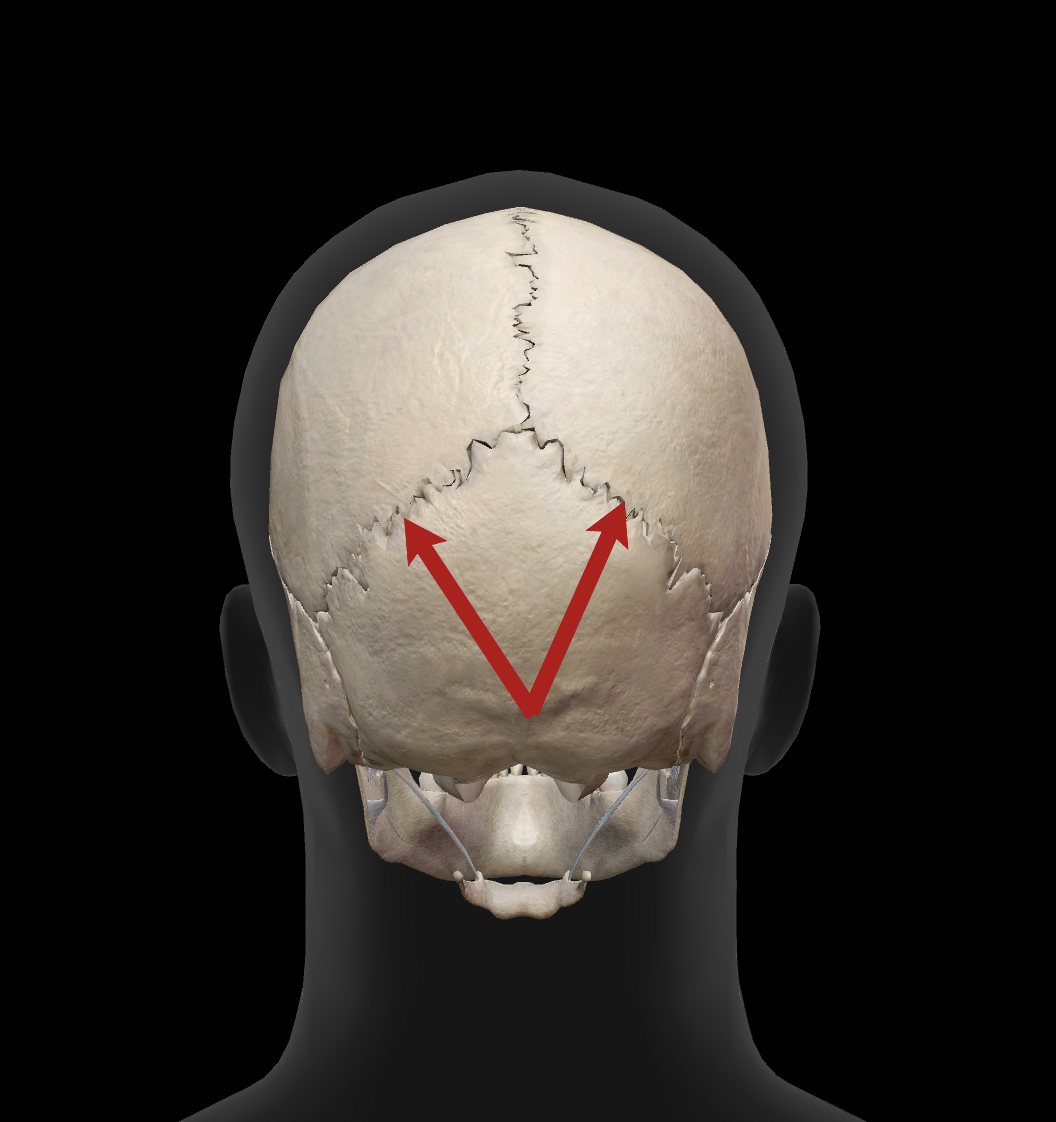

What is the name of this suture?

coronal suture

What is the name of this suture?

squamosal suture

What is the name of this suture?

sagittal suture

What is the name of this suture?

lambdoidal suture

What is the name of this feature?

external occipital protuberance

What is the name of this feature?

superior nuchal line

What is the name of this feature?

inferior nuchal line

What is the hole called?

foramen magnum

What is the name of this feature?

occipital condyles